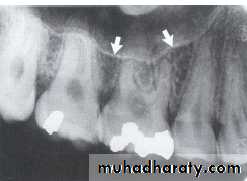

The maxillary sinus are paired cavities or compartments of bone located within the maxilla. The maxillary sinus are located above the maxillary permolars and molars teeth. Radiographically the sinus appears as a radiolucent area located above the apices of maxillary premolars and molars. The floor of sinus is composed of dense cortical bone and appear as radiopaque.

SEPTA WITHIN THE MAXILLARY SINUS:

Septa are bony wall that divided the maxillary sinus into compartment. Radiographically the septa appear as a radiopaque line within the sinus.

Nutrient Canals within Maxillary Sinus

Nutrient canals may be seen within maxillary sinuses. Nutrient canals are tiny, tubelike passageways through bone, which contain blood vessels and nerves that supply maxillary teeth and interdental areas. On a maxillary periapical image, a nutrient canal appears as a narrow radiolucent band bounded by two thin radiopaque lines.INVERTED Y